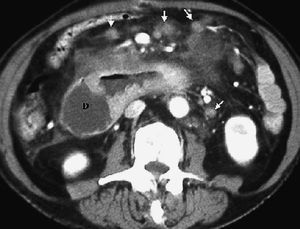

Fig. 18--Neurofibromas. (A) Ecografía. (B) Tomografía computarizada con contraste intravenoso en un paciente con enfermedad de von Recklinghausen. Se observan múltiples lesiones sólidas (*) en la pared duodenal (D). P: Páncreas.